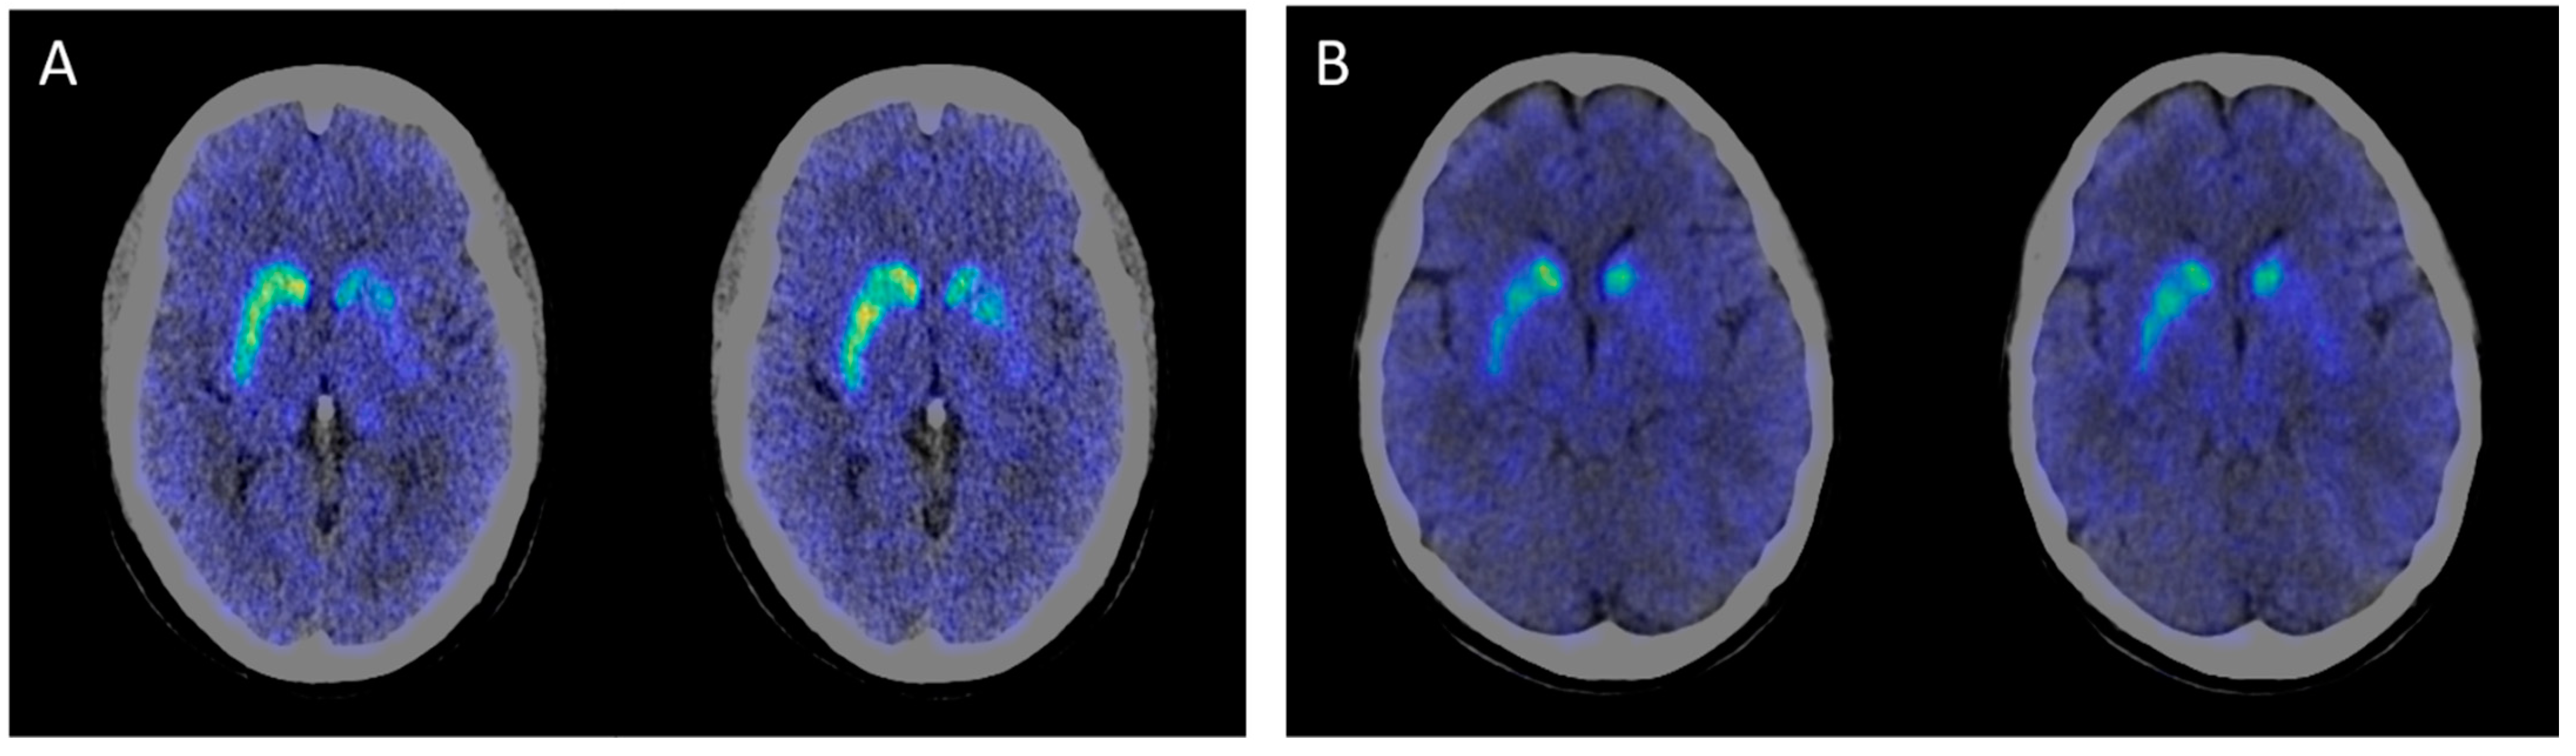

| 11C-CFT PET/CT results | NA | Decreased DAT uptake ratios in bilateral caudate and putamen, especially in the left side | NA | NA | NA | Decreased DAT uptake ratios in bilateral caudate and putamen, especially in the left side | NA |